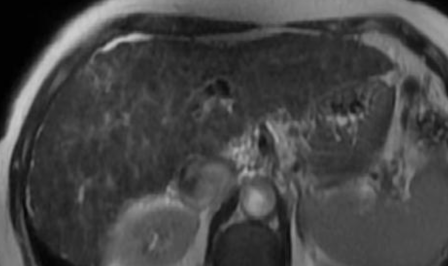

Imagerie

- N’est pas en soit un diagnostic visible en imagerie

- On voit surtout un Foie Fibrotique

- Pas d’anomalie visible des voies biliaires

- Oedeme périportal

- Adénopathies